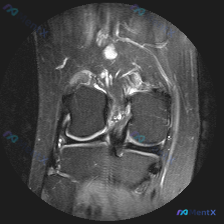

二、现有影像学发现(膝关节MRI T2序列冠状位单层面)

我先把所有客观发现整理出来:

- 骨骼与关节软骨:股骨远端、胫骨近端骨皮质连续,无骨折;骨髓信号均匀,无明显水肿/硬化;关节软骨完整,未见缺损剥脱

- 半月板:内外侧半月板都是正常低信号三角形结构,边界清晰,没有异常高信号延伸到关节面,本层面未见半月板撕裂或异常征象

- 韧带:内外侧副韧带走行连续,信号正常,结构完整;交叉韧带因体位限制显示不全,但可见纤维束影,无明显异常水肿信号

- 核心阳性发现:髁间窝上方、髌上囊区域可见大范围高信号影,提示存在明显关节腔积液,滑膜无明显结节增生或肥厚

第一眼看到问题,大家肯定先去找半月板,但看下来本层面半月板完全正常,反而有一个很突出的异常就是大量关节积液。

这里有个很明确的矛盾:初始怀疑半月板异常,但影像不支持,反而提示了另一个核心问题——不明原因膝关节积液。